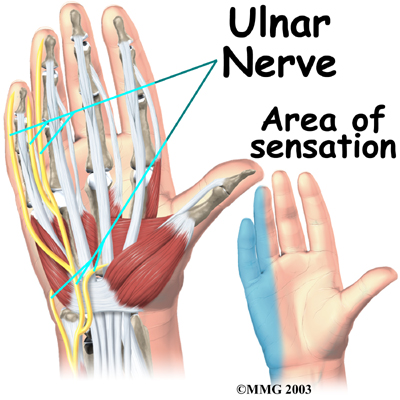

The travels through a separate tunnel, called Guyon's canal. This tunnel is formed by two carpal bones (the pisiform and hamate), and the ligament that connects them.

The travels through a separate tunnel, called Guyon's canal. This tunnel is formed by two carpal bones (the pisiform and hamate), and the ligament that connects them.

After passing through the canal, the ulnar nerve branches out to supply feeling to the little finger and half the ring finger.

Branches of this nerve also supply the small muscles in the palm and the muscle that pulls the thumb toward the palm.